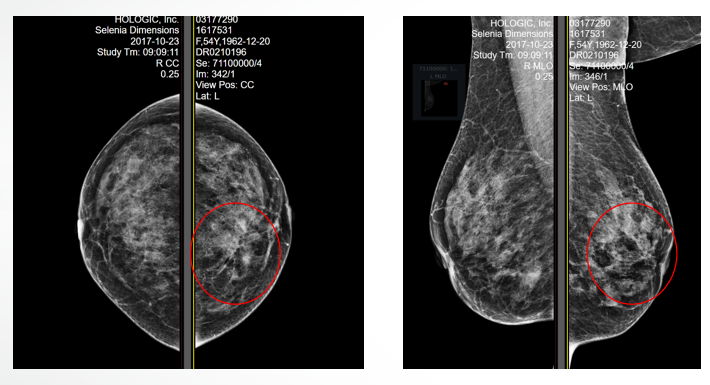

乳腺X线示:左乳内上象限见多发簇状卵圆形结节影,边缘略模糊伴毛刺,大部分边界可见。诊断:左乳内上象限簇状多发结节,性质不肯定,建议活检,BI-RADS 4B。

乳腺增强MRI示:左乳上象限见一肿块,大小约21.6mm*11.8mm,边界不光整、分叶,周围组织牵拉改变,DWI呈可见弥散受限改变,增强后肿块明显强化,乳头皮肤增厚、强化、回缩。注射造影剂后动态强化曲线呈II型(平台型)。

诊断:左乳肿块,BI-RADS 4B。